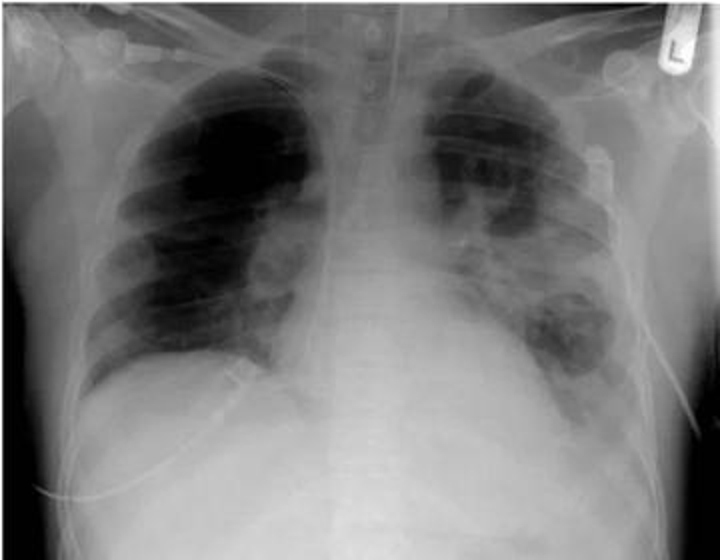

14岁男孩辛佳昊突患葡萄球菌性肺炎,情况危急!医院ICU人工肺维持生命,每日治疗费高达两万多元!父母急求救,社会热心伸出援手。

病情起伏,风险未除。尽管孩子的病情有所好转,但仍然面临着不小的风险,医治之路尚未结束。他们仍需要持续的治疗和支持。